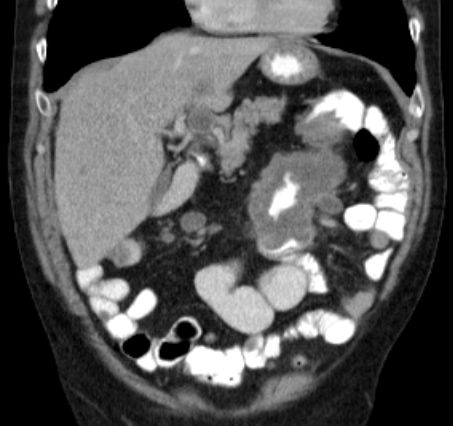

Stenosierender Tumor der linken Flexur mit Ileus.